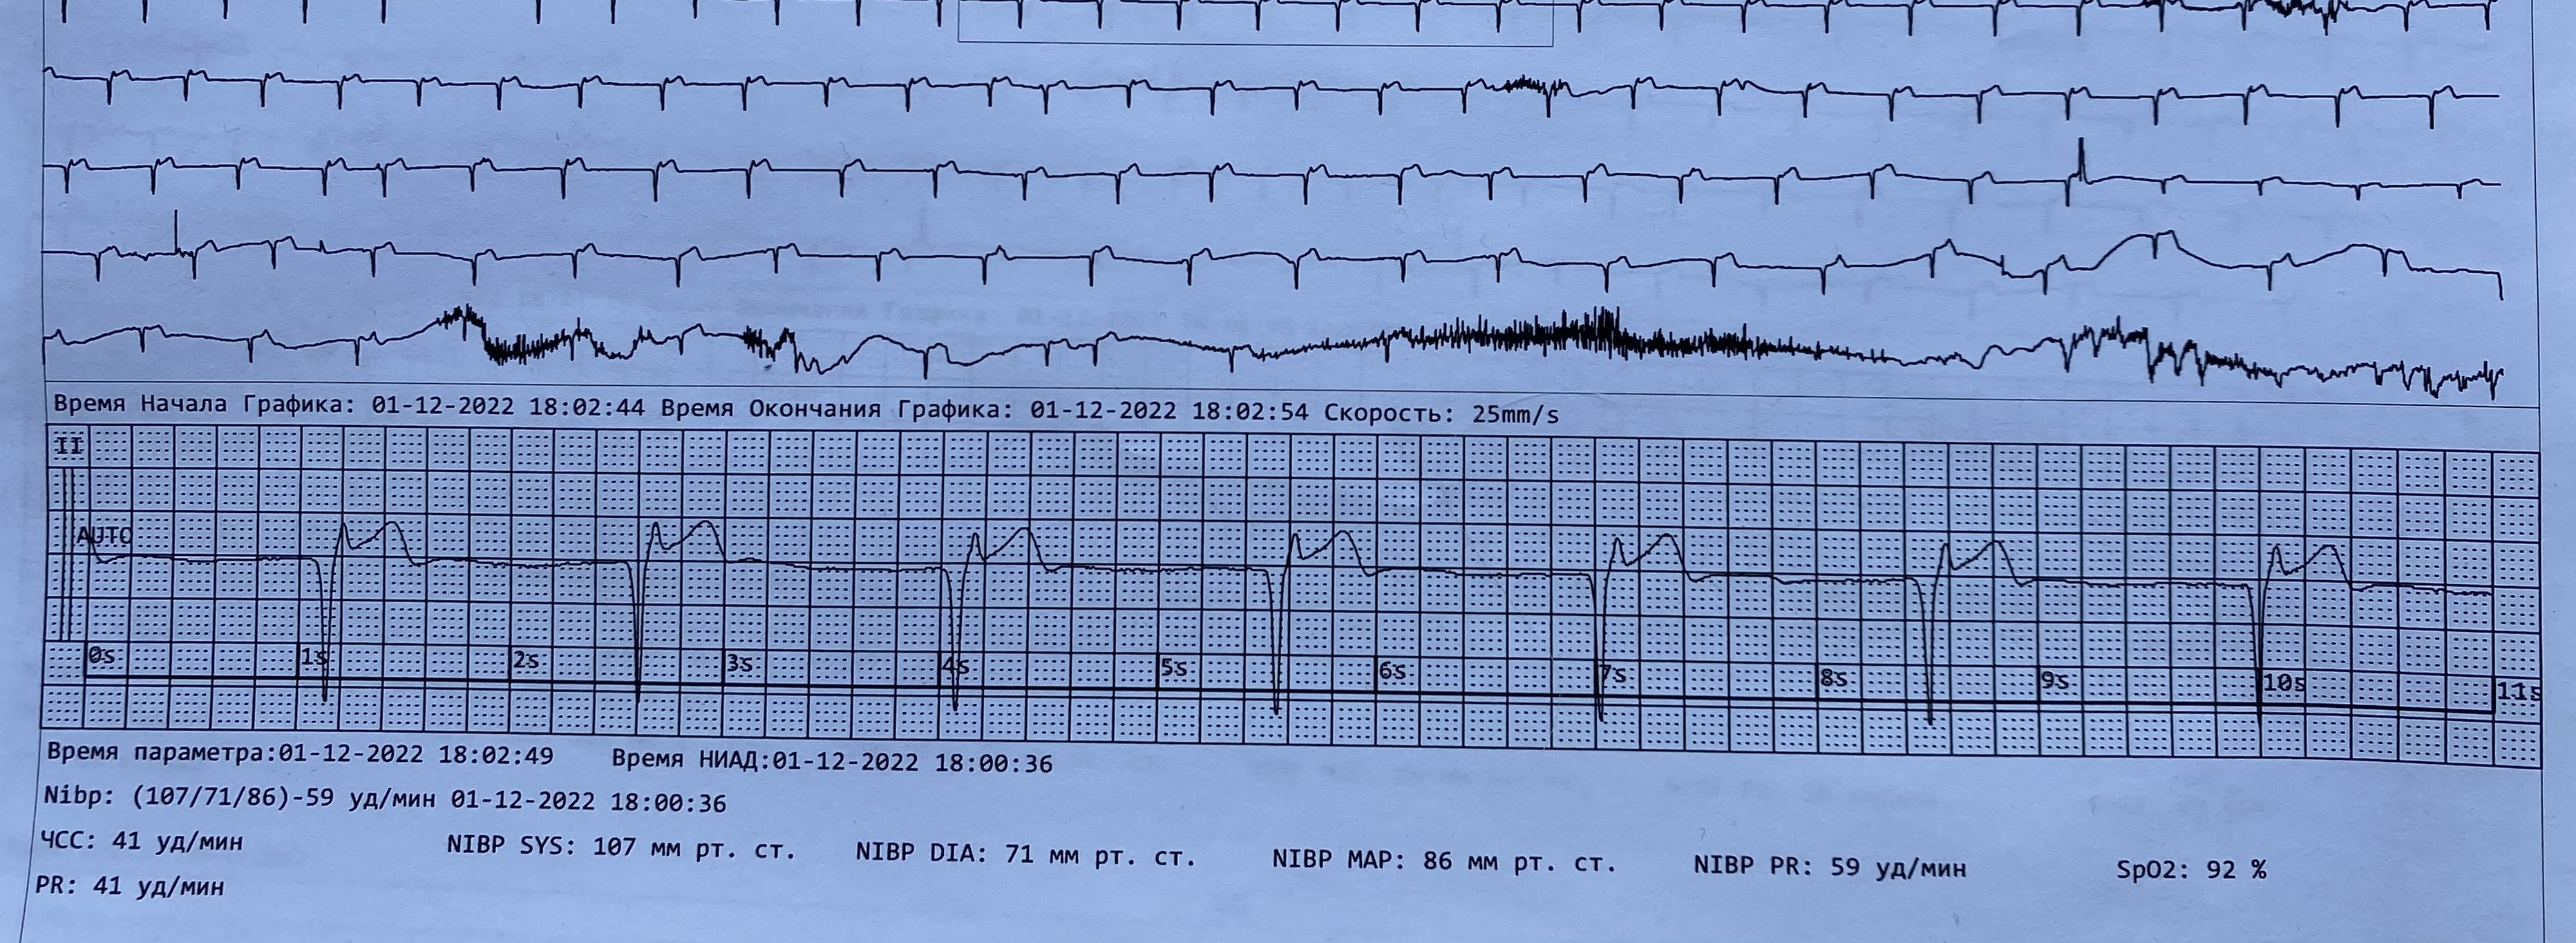

Предсердный переходит в изоритмическую АВ диссоциацию

Обсуждалось здесь https://vk.com/club84409679?w=wall-84409679_13425%2Fall